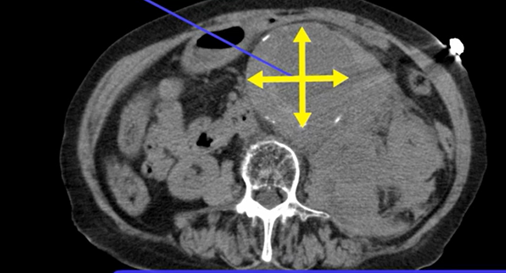

80歳女性。腰背部痛を訴え、来院時にはショック状態で意識レベルが低下していた。

補液にてバイタルを安定させながら単純CT施行。

腹部大動脈の拡張と、周囲に紅斑に広がる血腫あり。

診断:腹部大動脈破裂

※腹部大動脈瘤の測定の仕方

大動脈長軸に直行する断面で長径と短径を測る。